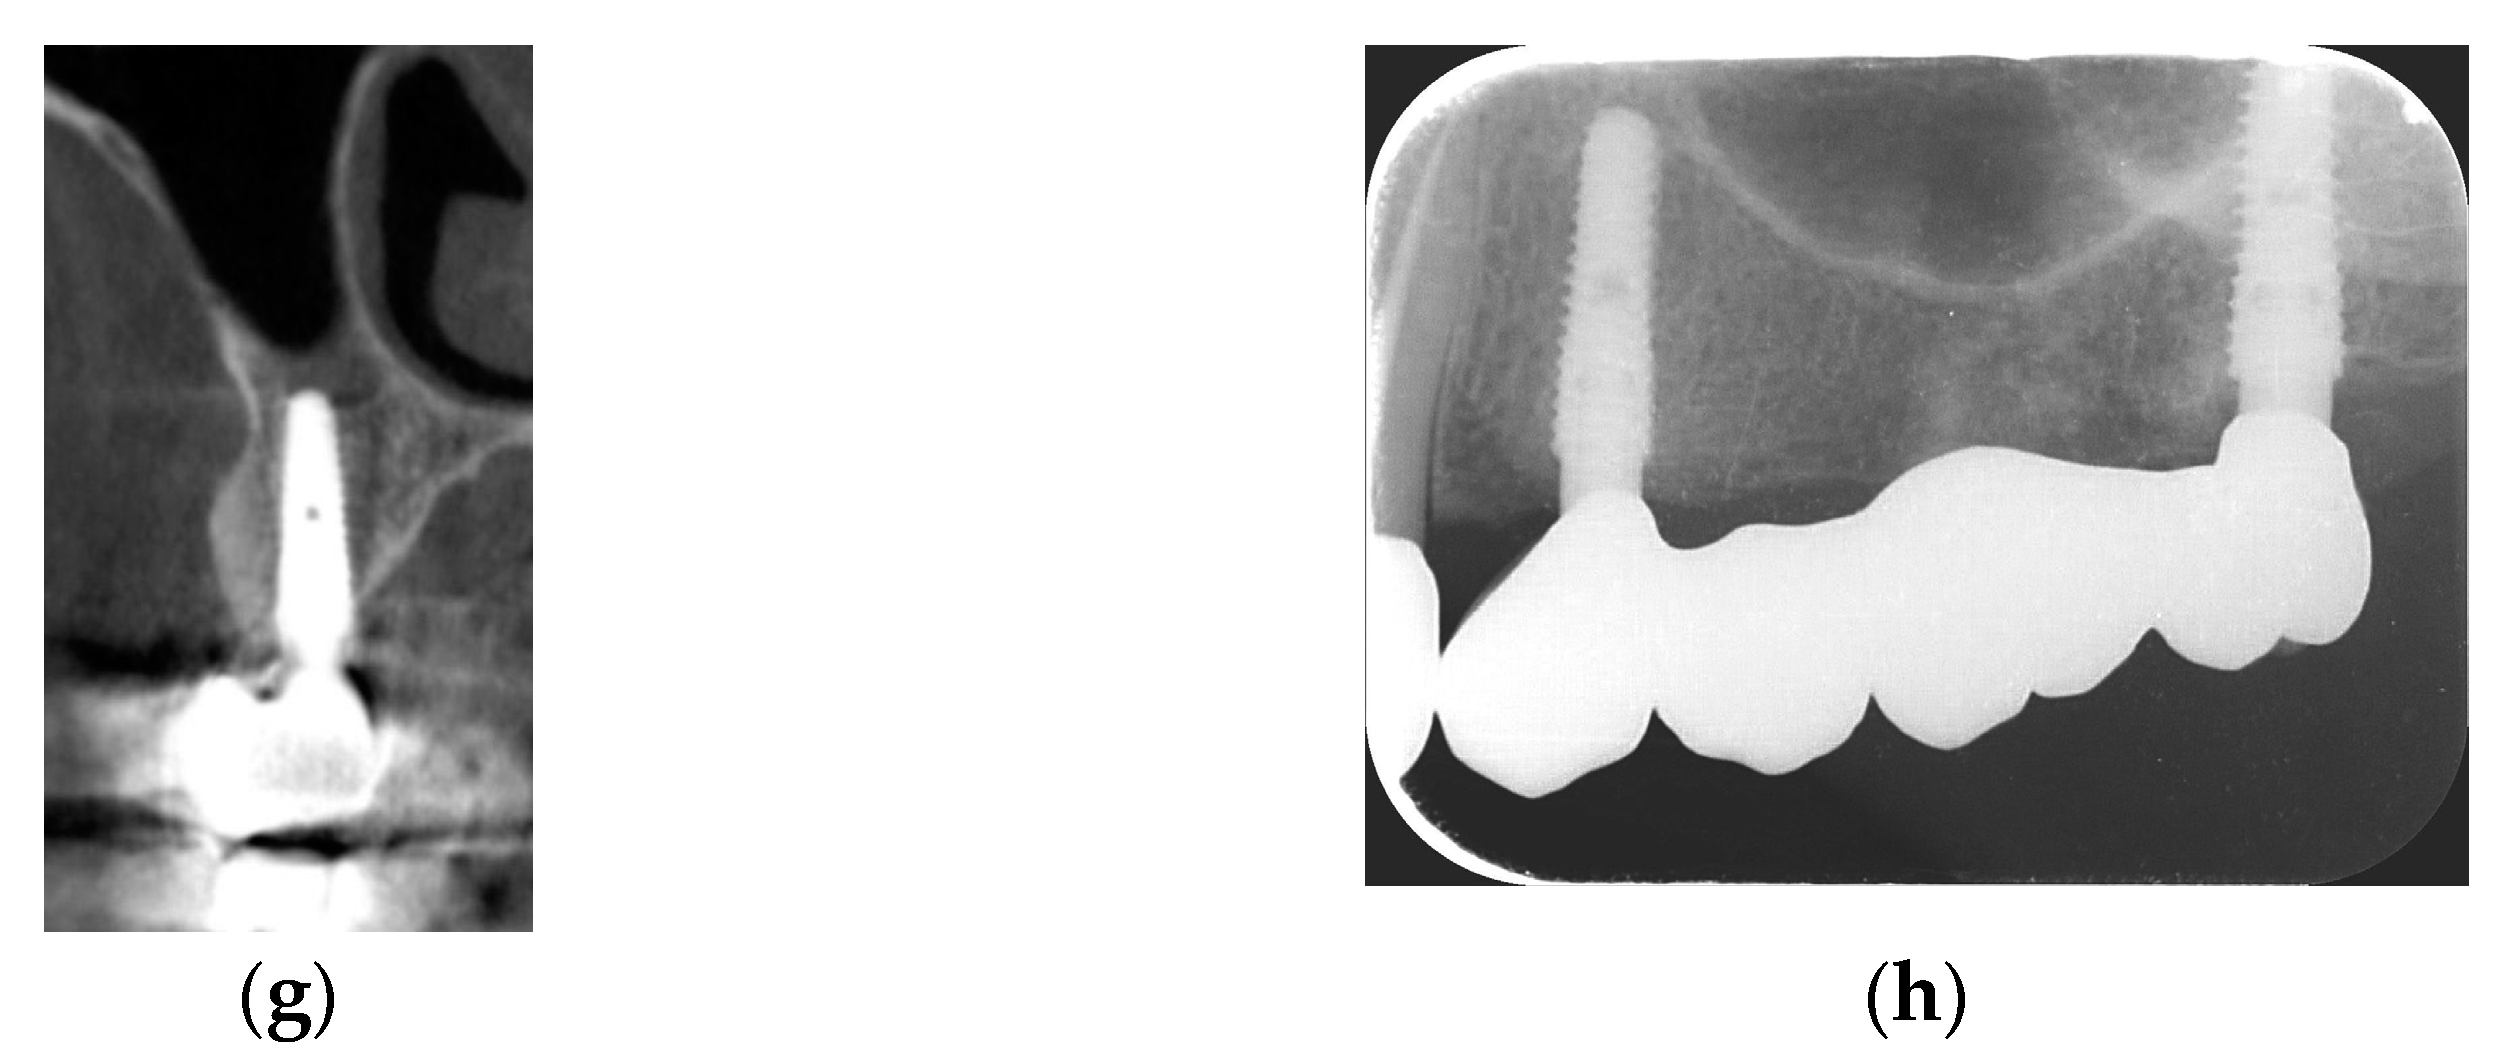

2.2.1. Horizontal and Vertical GBR Using F.I.R.S.T.

2.2.2. Immediate Implant Placement Using F.I.R.S.T.

2.2.3. ARP and Delayed Implant Placement Using F.I.R.S.T.

- Foti, V.; Rossi, R. Fibrinogen-induced regeneration sealing technique (first) an improvement and modification of traditional gbr: A report of two cases. Mod. Res. Dent. 2020, 5, 476–485. [Google Scholar]

- Foti, V.; Savio, D.; Rossi, R. One-time cortical lamina: A new technique for horizontal ridge augmentation. A Case Ser. Br. J. Healthc. Med. Res. 2021, 8, 22–30. [Google Scholar] [CrossRef]

- Foti, V. Fibrinogen-induced regeneration sealing technique (f.I.R.S.T.). In Building Better Bone: A Comprehensive Guide to gbr Techniques; Rossi, R., Ed.; Quintessence Publishing: Batavia, IL, USA, 2024; pp. 210–227. [Google Scholar]

- Faro, L.L.; Strappa, E.M.; Carù, F.G.; Nanni, M.; Invernizzi, M.; Testori, T. Rigenerazione ossea guidata con tecnica first (fibrin-induced regeneration sealing technique). Case report con evidenze istologiche. Quintessenza Internazionale Riv. Di Odontoiatr. 2023, 37, 10–21. [Google Scholar]